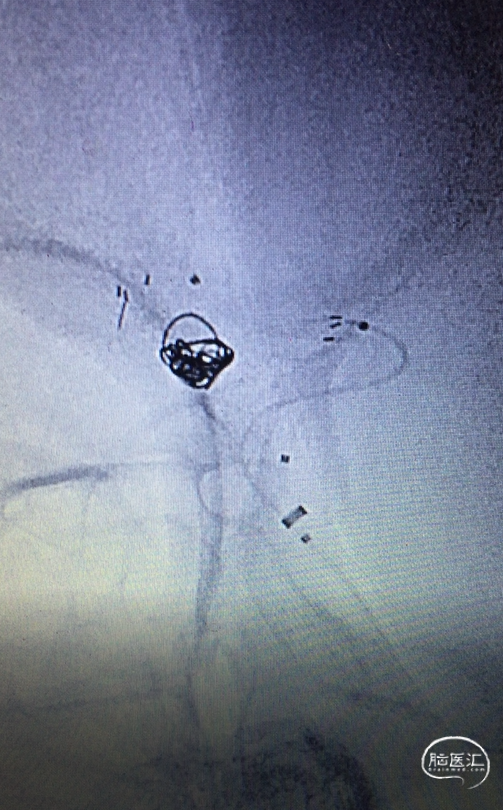

穿网孔超选

将直头SL-10穿过Atlas网眼超选入动脉瘤右侧分叶(左图),蒙片显示Altas形态及双微导管头位置,到达理想位置(右图)。

栓塞过程

直头SL-10及S头SL-10先后交互填圈,分区致密栓塞动脉瘤。